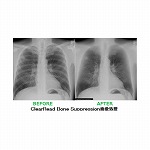

【胸部X線画像から骨組織を透過させ、肺組織の視認性を大幅に向上。肺結節や異常陰影の見落とし防止、検出率向上への期待】

東陽テクニカ ClearRead BSは院内で撮影される胸部X線画像に対し肋骨・鎖骨等の骨組織を透過させ、肺組織の視認性を向上させる独自の画像処理技術です。骨組織に重なり検出が困難であった肺結節や異常陰影の視認性を飛躍的に向上させます。

●肺組織の視認性を劇的に向上させる骨組織透過処理。

●骨組織透過に加え、画質改善処理を同時実施。